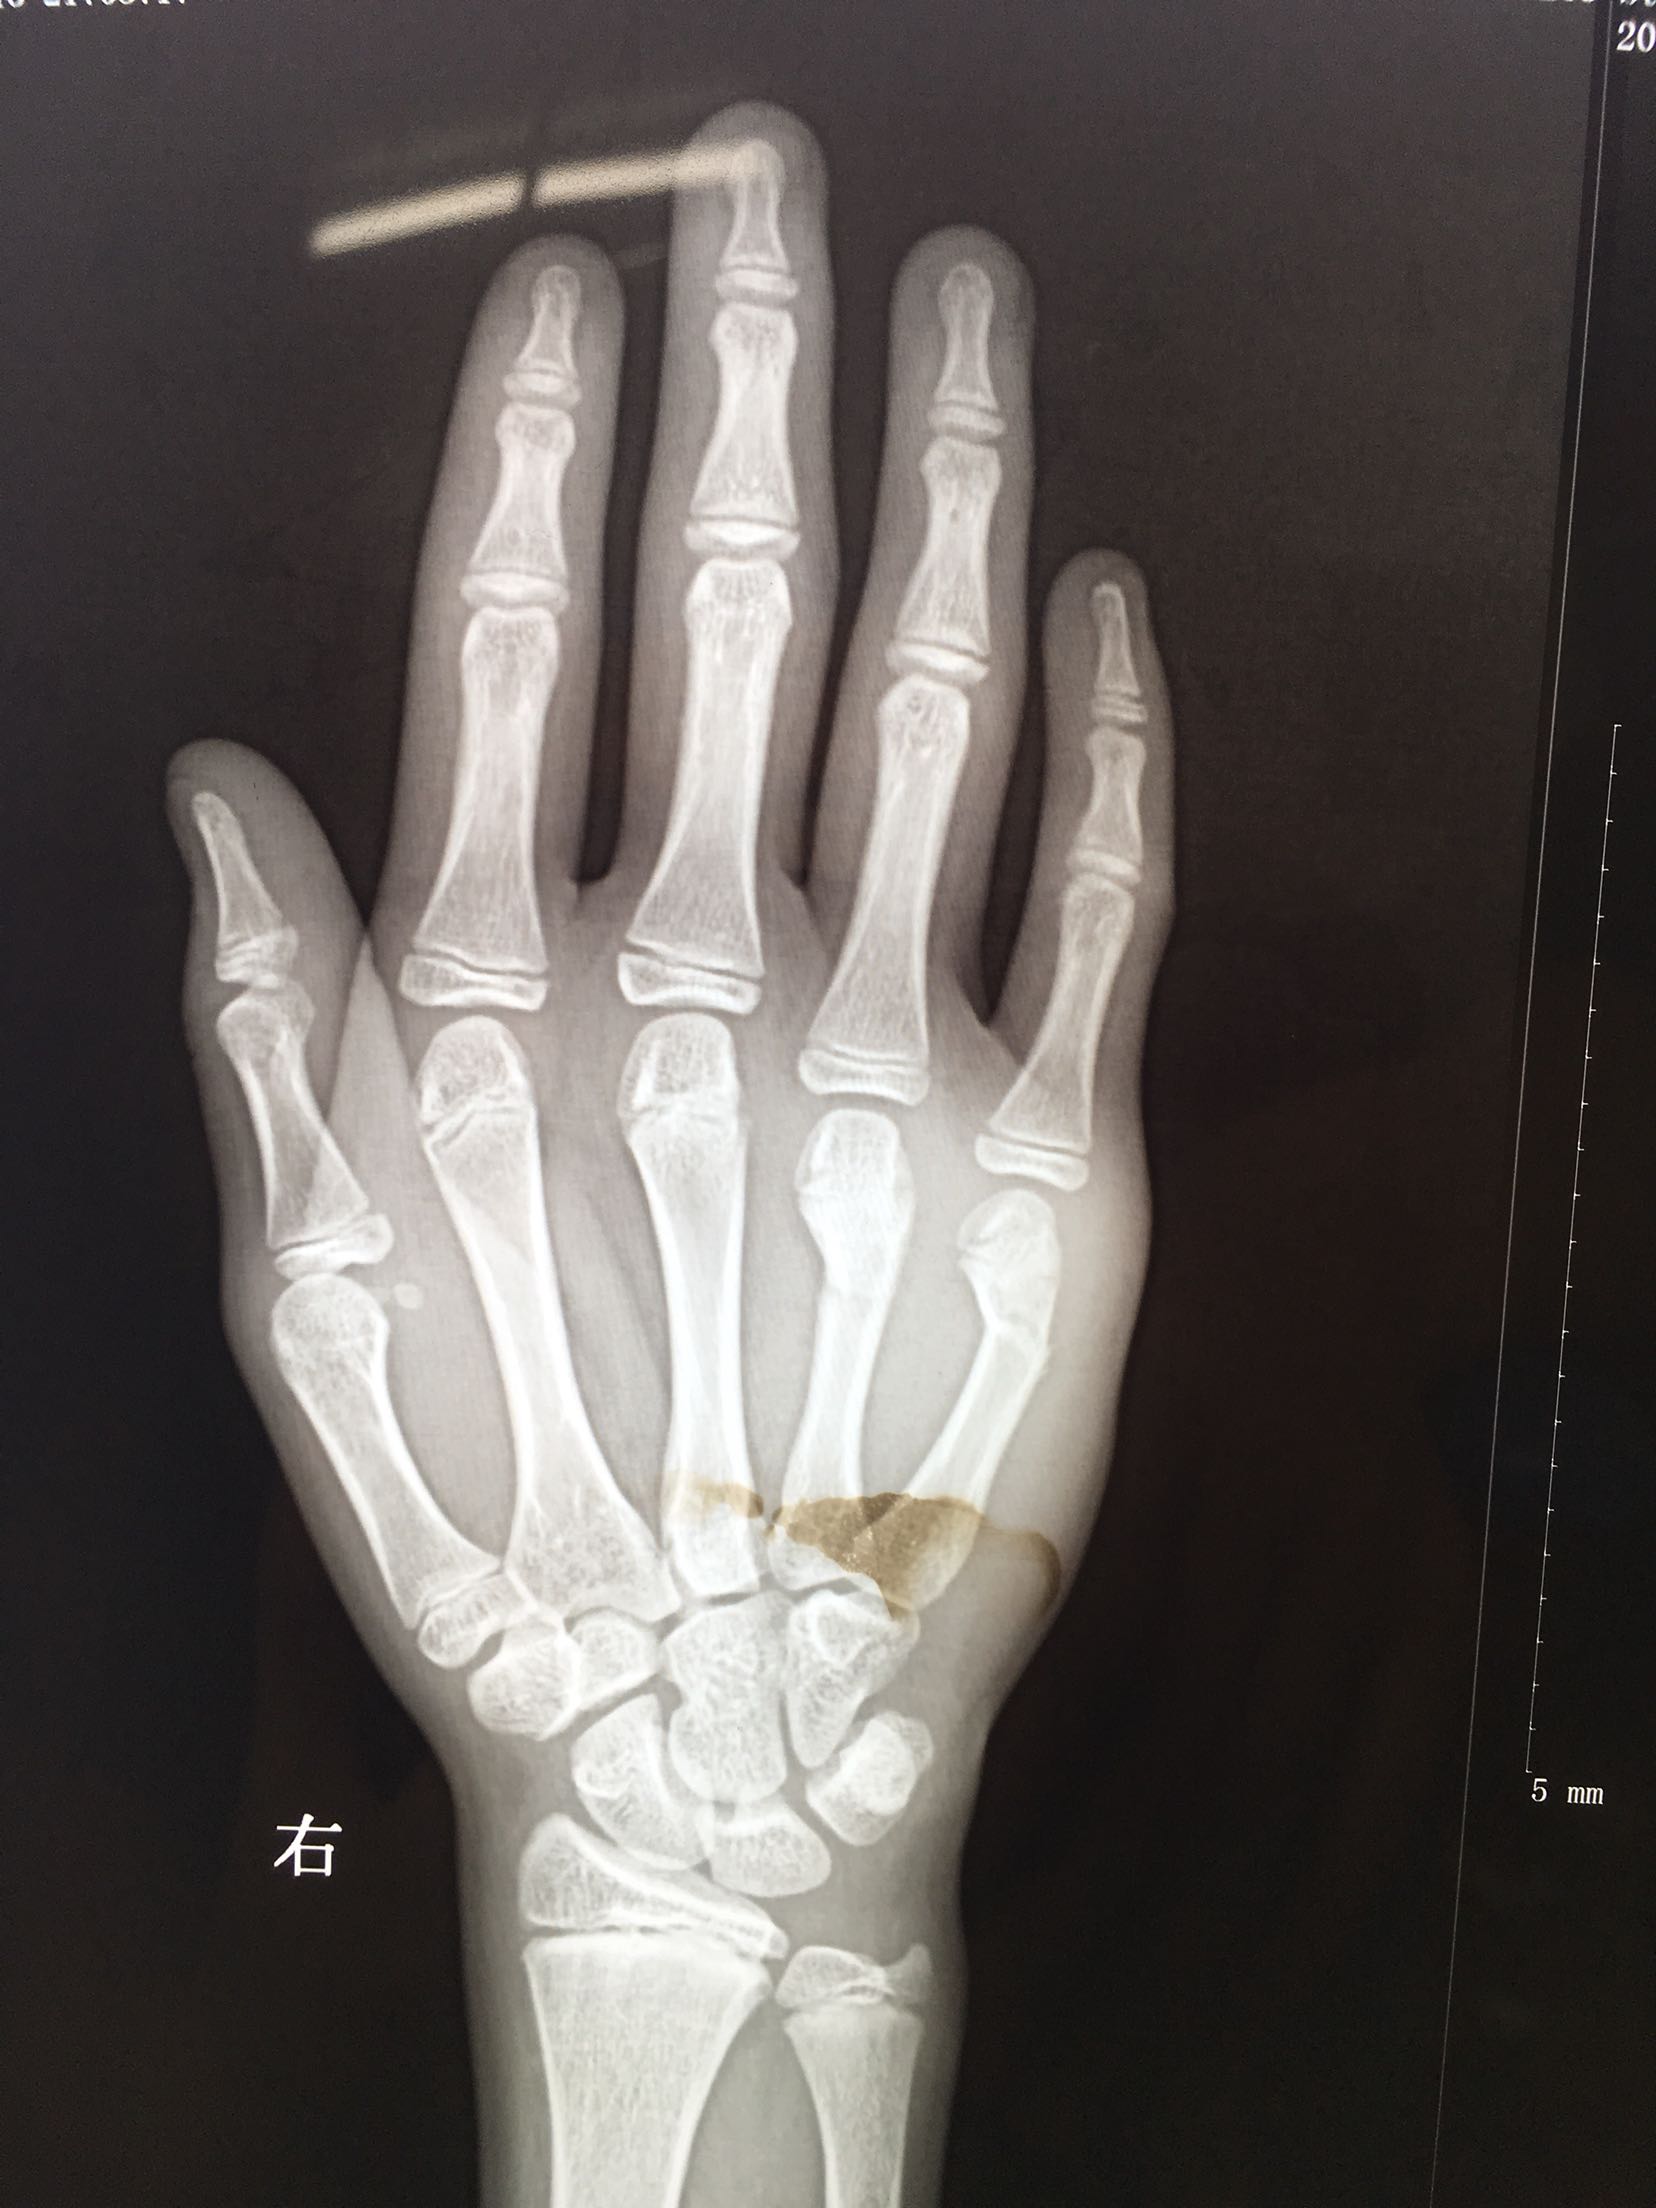

右第四,五掌骨骨折(微创)

患者,男,13岁,撞伤后右手肿痛,活动受限1天入院。

右手肿胀明显,局部皮色青紫,皮温稍高,第四,五掌骨头处压痛,纵叩痛阳性,掌指关节活动受限,末梢血运感觉正常。

完善检查,在臂丛麻醉下行闭合复位内固定术,术后抗炎,消肿止痛等对症处理,右手石膏托制动。